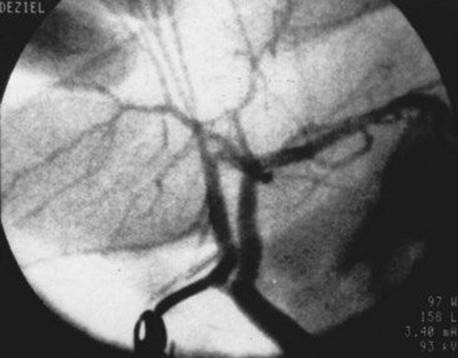

4 In this intraoperative cholangiogram, the arrow points to what duct?

Comments

Variations in the anatomy of the extrahepatic bile ducts occur commonly. The surgeon must be cognizant of these variations and learn to recognize and identify them to prevent inadvertent injury to the bile ducts during cholecystectomy. Approximately two thirds of individuals have the “textbook” anatomy, with the anterior (segments V and VIII) and posterior (segments VI and VII) sectional ducts from the right joining to form the main right hepatic duct, which then joins the main left hepatic duct to form the common hepatic duct. In 15% to 25% of individuals, the anterior or posterior sectional duct from the right lobe inserts separately into the common hepatic duct. When the posterior duct inserts separately, it is usually at a greater distance caudally from the junction of the left duct and the other right duct than when the anterior duct inserts separately. This duct is therefore at risk for injury during cholecystectomy if the anatomy is not recognized.

One of the most common variations in cystic duct anatomy is direct insertion into one of these separately inserting right hepatic ducts, as the pictured cholangiogram demonstrates. The terms “crossover duct” and “accessory duct” are misnomers for this arrangement. True accessory ducts are rare and occur when there is embryologic duplication of the bud that forms the bile ducts and liver.